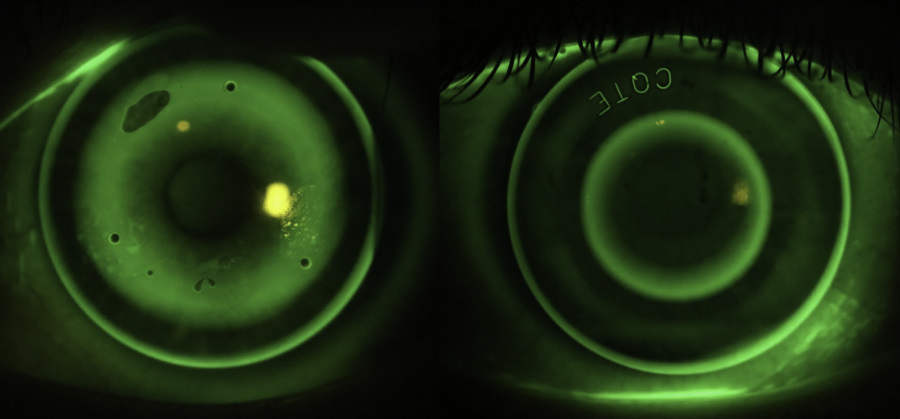

A comparison of orthoK lens designs. Left: An ‘adult’ orthokeratology lens (BE, Capricornia, AUS). BOZD >6mm, e=0. Right: A customised lens for myopia control (Eyespace Forge design, CLC, NZ) BOZD 5.5mm, e=0.99

When fitting an adult with ortho-k we want to minimise this paracentral steepening as it negatively affects vision due to spherical aberration and increased halos and glare at night when the pupil enlarges. Normal orthokeratology lenses tend to have a large spherical back-optic zone radius of 6mm or greater to facilitate this.

Lately most ortho-k experts around the world are using customised myopia control ortho-k lenses with the primary design consideration being to maximise the plus power of the peripheral pupillary zone. This typically involves smaller back optic zone diameters of 5-5.5mm (or smaller if the child has a small pupil) with aspheric base-curves. These lenses create a highly aspheric, small diameter treatment zone with a steeper paracentral ring. Amazingly vision is still great with these lens designs, in a similar way that centre-distance multifocal soft contact lenses are well tolerated by adults.